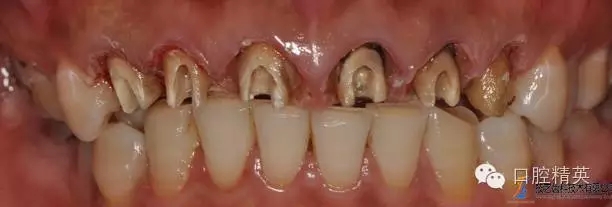

主訴:重新修復(fù)上前牙?,F(xiàn)病史:患者上前牙8年前曾在外院烤瓷冠修復(fù) 牙齦腫脹近日加劇來我院就診。

原金屬烤瓷冠

原金屬烤瓷牙咬頜觀